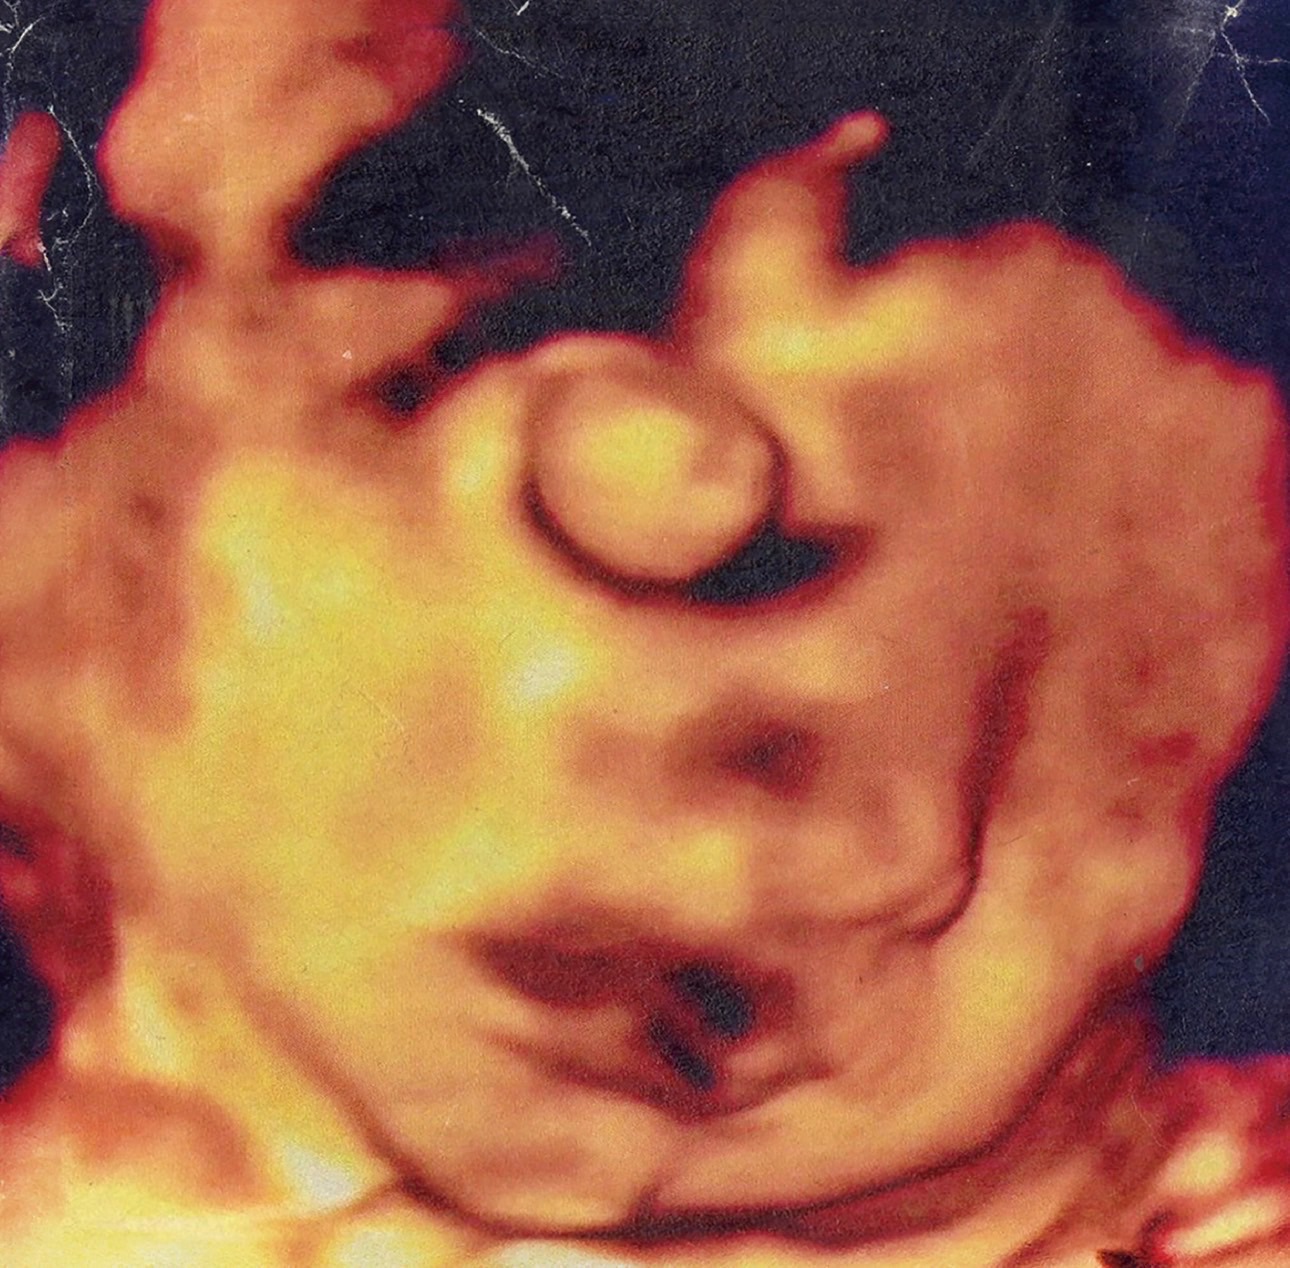

大阪ベアーズを拠点に活動、天国注射の初アルバムは“耐え難い現実に向かい合う人”に捧ぐ(画像・動画ギャラリー 2/4) 前へ 次へ 天国注射「春彦」ジャケット [記事に戻る] 前の画像 天国注射 次の動画 天国注射「idiot riot」MV この画像のタグ 天国注射 この記事の画像・動画(全4件) × 142 この記事に関するナタリー公式アカウントの投稿が、SNS上でシェア / いいねされた数の合計です。 28 96 18 シェア 記事へのコメント(7件) 読者の反応 142 7 Sanjay Verma @sanjayverma148 @natalie_mu ☺️❤️ コメントを読む(7件)